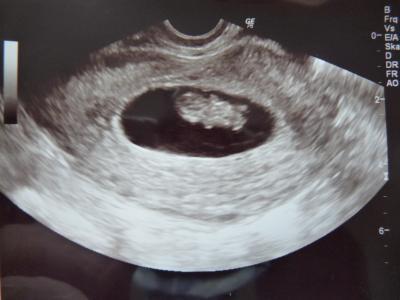

Hallo Mädels, vielen lieben Dank fürs Daumendrücken, ich habe noch im Wartezimmer Eure lieben Worte gelesen und das hat mich echt beruhigt Ich habe ein wunderschönes Gummibärchen und es ist jetzt 2,26cm groß bei ET 8+5. Erst hat es ich nicht bewegt und dann meinte meine FÄ, mal schauen ob wir das Gummibärchen nicht mal wecken können und dann plötzlich hat es sich bewegt. Das war absolut bezaubernd, ich bin hin und weg und total verliebt. Mein Mann war endlich mal mit und auch total begeistert, dass man schon so viel sehen konnte. Damals bei meiner ersten SSW vor 8 Jahren, war es eher ein raten als gucken, vor allem am Anfang. Nochmals tausend Dank und fühlt Euch alle gedrückt

Bild zu Danke fürs Daumendrücken und Fa Bericht - Forum für September - Mamis

Oh wie süss... sieht aber echt total aus wie ein Gummibär, so wie es da so liegt Und ein sehr schönes klares Foto, meine sind leider nicht so gestochen scharf und da musste man in den ersten Wochen immer etwas mehr rätseln und gucken Ich hoffe mein Krümel ist morgen auch wieder gut zu sehen und er macht mal en bißchen Action *grins* Letztes Mal hat er gepennt Aber vielleicht ist er mit 13+5 ja etwas aktiver als in der 9.Woche LG Sarah P.S. Wie hat deine FÄ den Krümel denn "wach" bekommen --> damit ich mir den Trick für morgen schon mal merken kann, falls der kleinen "Faulpelz" wieder schläft